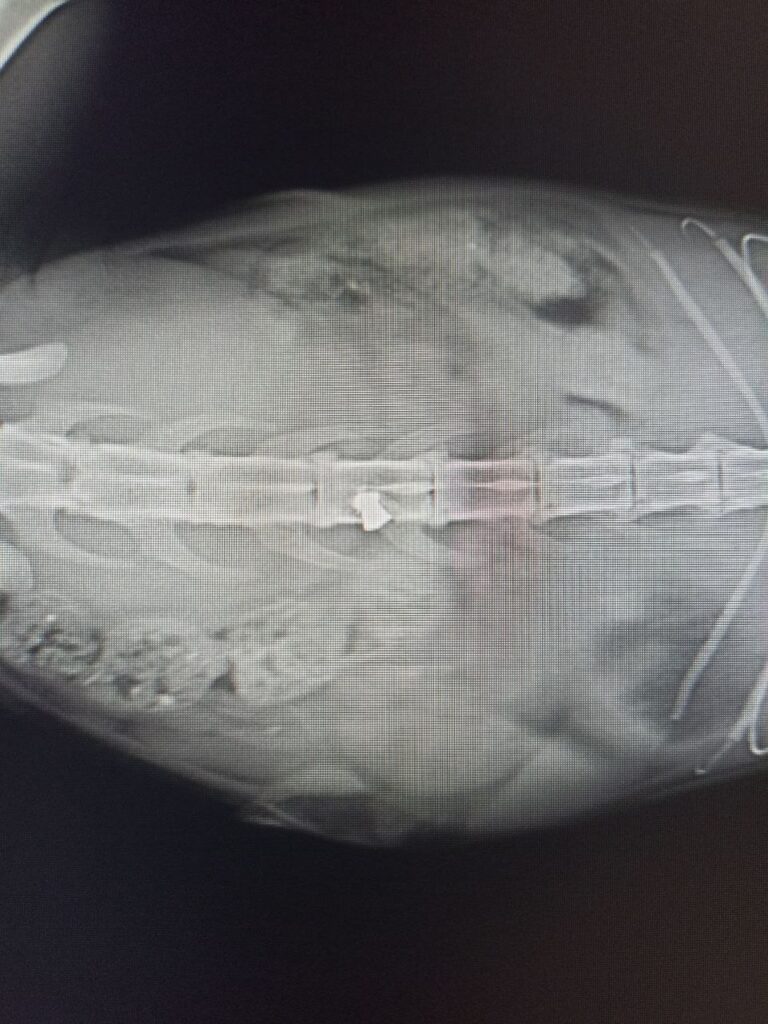

Поліціянти зафіксували випадок жорстокого поводження з тваринами. 10 квітня в районі Київського шосе, 70, невідомі вистрілили у голову безпритульному коту. Куля влучила у спинний мозок.

За словами місцевих мешканців, поранений кіт намагався доповзти до під’їзду, де його і знайшли. Тварині, яку назвали Кім, уже провели операцію, проте його стан залишається критичним. У кота паралізована половина тіла, він не може самостійно функціонувати та потребує постійного медичного догляду та тривалої реабілітації.

«Зараз Кім бореться за своє життя. Йому провели операцію, залишається тільки чекати, але він на волосині від смерті. Він повністю не відчуває половину свого тіла. Найстрашніше те, що він не може ходити в туалет сам, постійно з катетером, а це інфекції, ураження нирок і смерть».